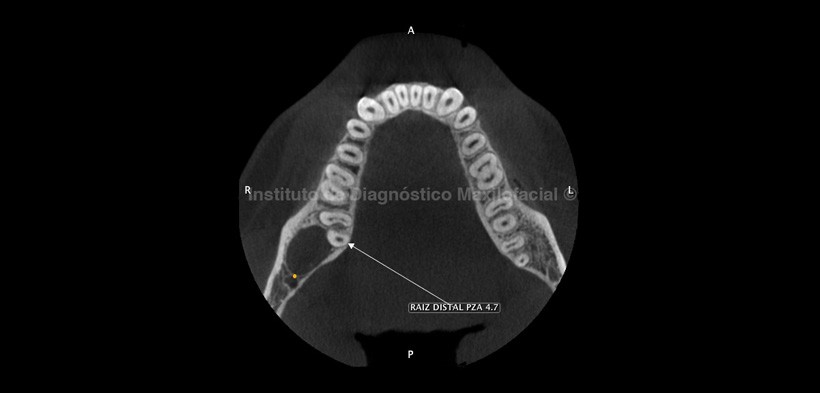

Al estudio con tomografía volumétrica, en el corte tangencial (Fig. 2) confirmamos la formación quística envolviendo la corona de la pieza 4.8, condicionando la posición invertida de esta, con las raíces próximas al borde anterior de la rama ascendente. En el corte axial (Fig. 3) se observa el proceso osteolítico en contacto con la raíz distal de la pieza 4.7, así como el adelgazamiento de la tabla ósea lingual. En el corte transaxial (Fig. 4) se observa el origen de la lesión a nivel de la unión cemento-adamantina (UCA) de la pieza 4.8 y el desplazamiento basal del conducto dentario inferior.